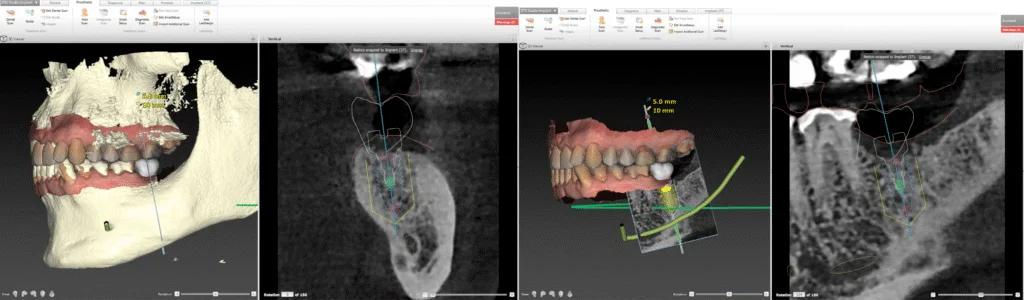

À partir des données recueillies lors de la première consultation ( Cone Beam 3D, empreinte optique, examen clinique et anamnèse médicale ) une planification implantaire tridimensionnelle est réalisée à l’aide de logiciels spécialisés.

Cette étape permet de :

- Positionner virtuellement l’implant de manière idéale, en respectant à la fois les contraintes anatomiques (canal mandibulaire, sinus, racines adjacentes, structures nerveuses) et les contraintes prothétiques (axe d’émergence, espace disponible, équilibre occlusal, esthétique) ;

- Anticiper la forme et le volume de la future restauration prothétique pour garantir une intégration à la fois fonctionnelle et harmonieuse ;

- Évaluer la nécessité de procédures complémentaires, telles qu’une greffe osseuse, une régénération osseuse guidée ou une greffe de tissu gingival, lorsque les conditions locales le justifient.

Cette planification rigoureuse permet également de définir :

- le type d’implant (longueur, diamètre, design),

- la séquence chirurgicale adaptée,

- la profondeur et l’angulation de l’insertion,

- ainsi que les modalités de temporisation prothétique (mise en charge immédiate ou différée selon les cas).

Lorsque les conditions cliniques le permettent, le chirurgien peut recourir à une chirurgie guidée, reposant sur l’utilisation d’une gouttière de guidage statique imprimée en 3D ou d’un système de guidage chirurgical dynamique. Ces dispositifs contribuent à améliorer la précision du geste opératoire, à minimiser les traumatismes chirurgicaux, et à réduire les suites post-opératoires, tout en renforçant la sécurité du patient.